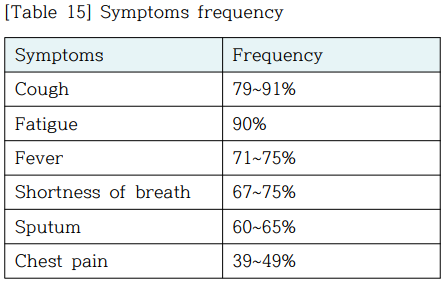

2. 세균성 및 바이러스성 폐렴 (Bacterial and Viral cased of pneumonia) 증상

일반적으로 유사한 증상이 나타난다.

일부 원인은 고전적이지만 비특이적인 임상 특성과 관련있다.